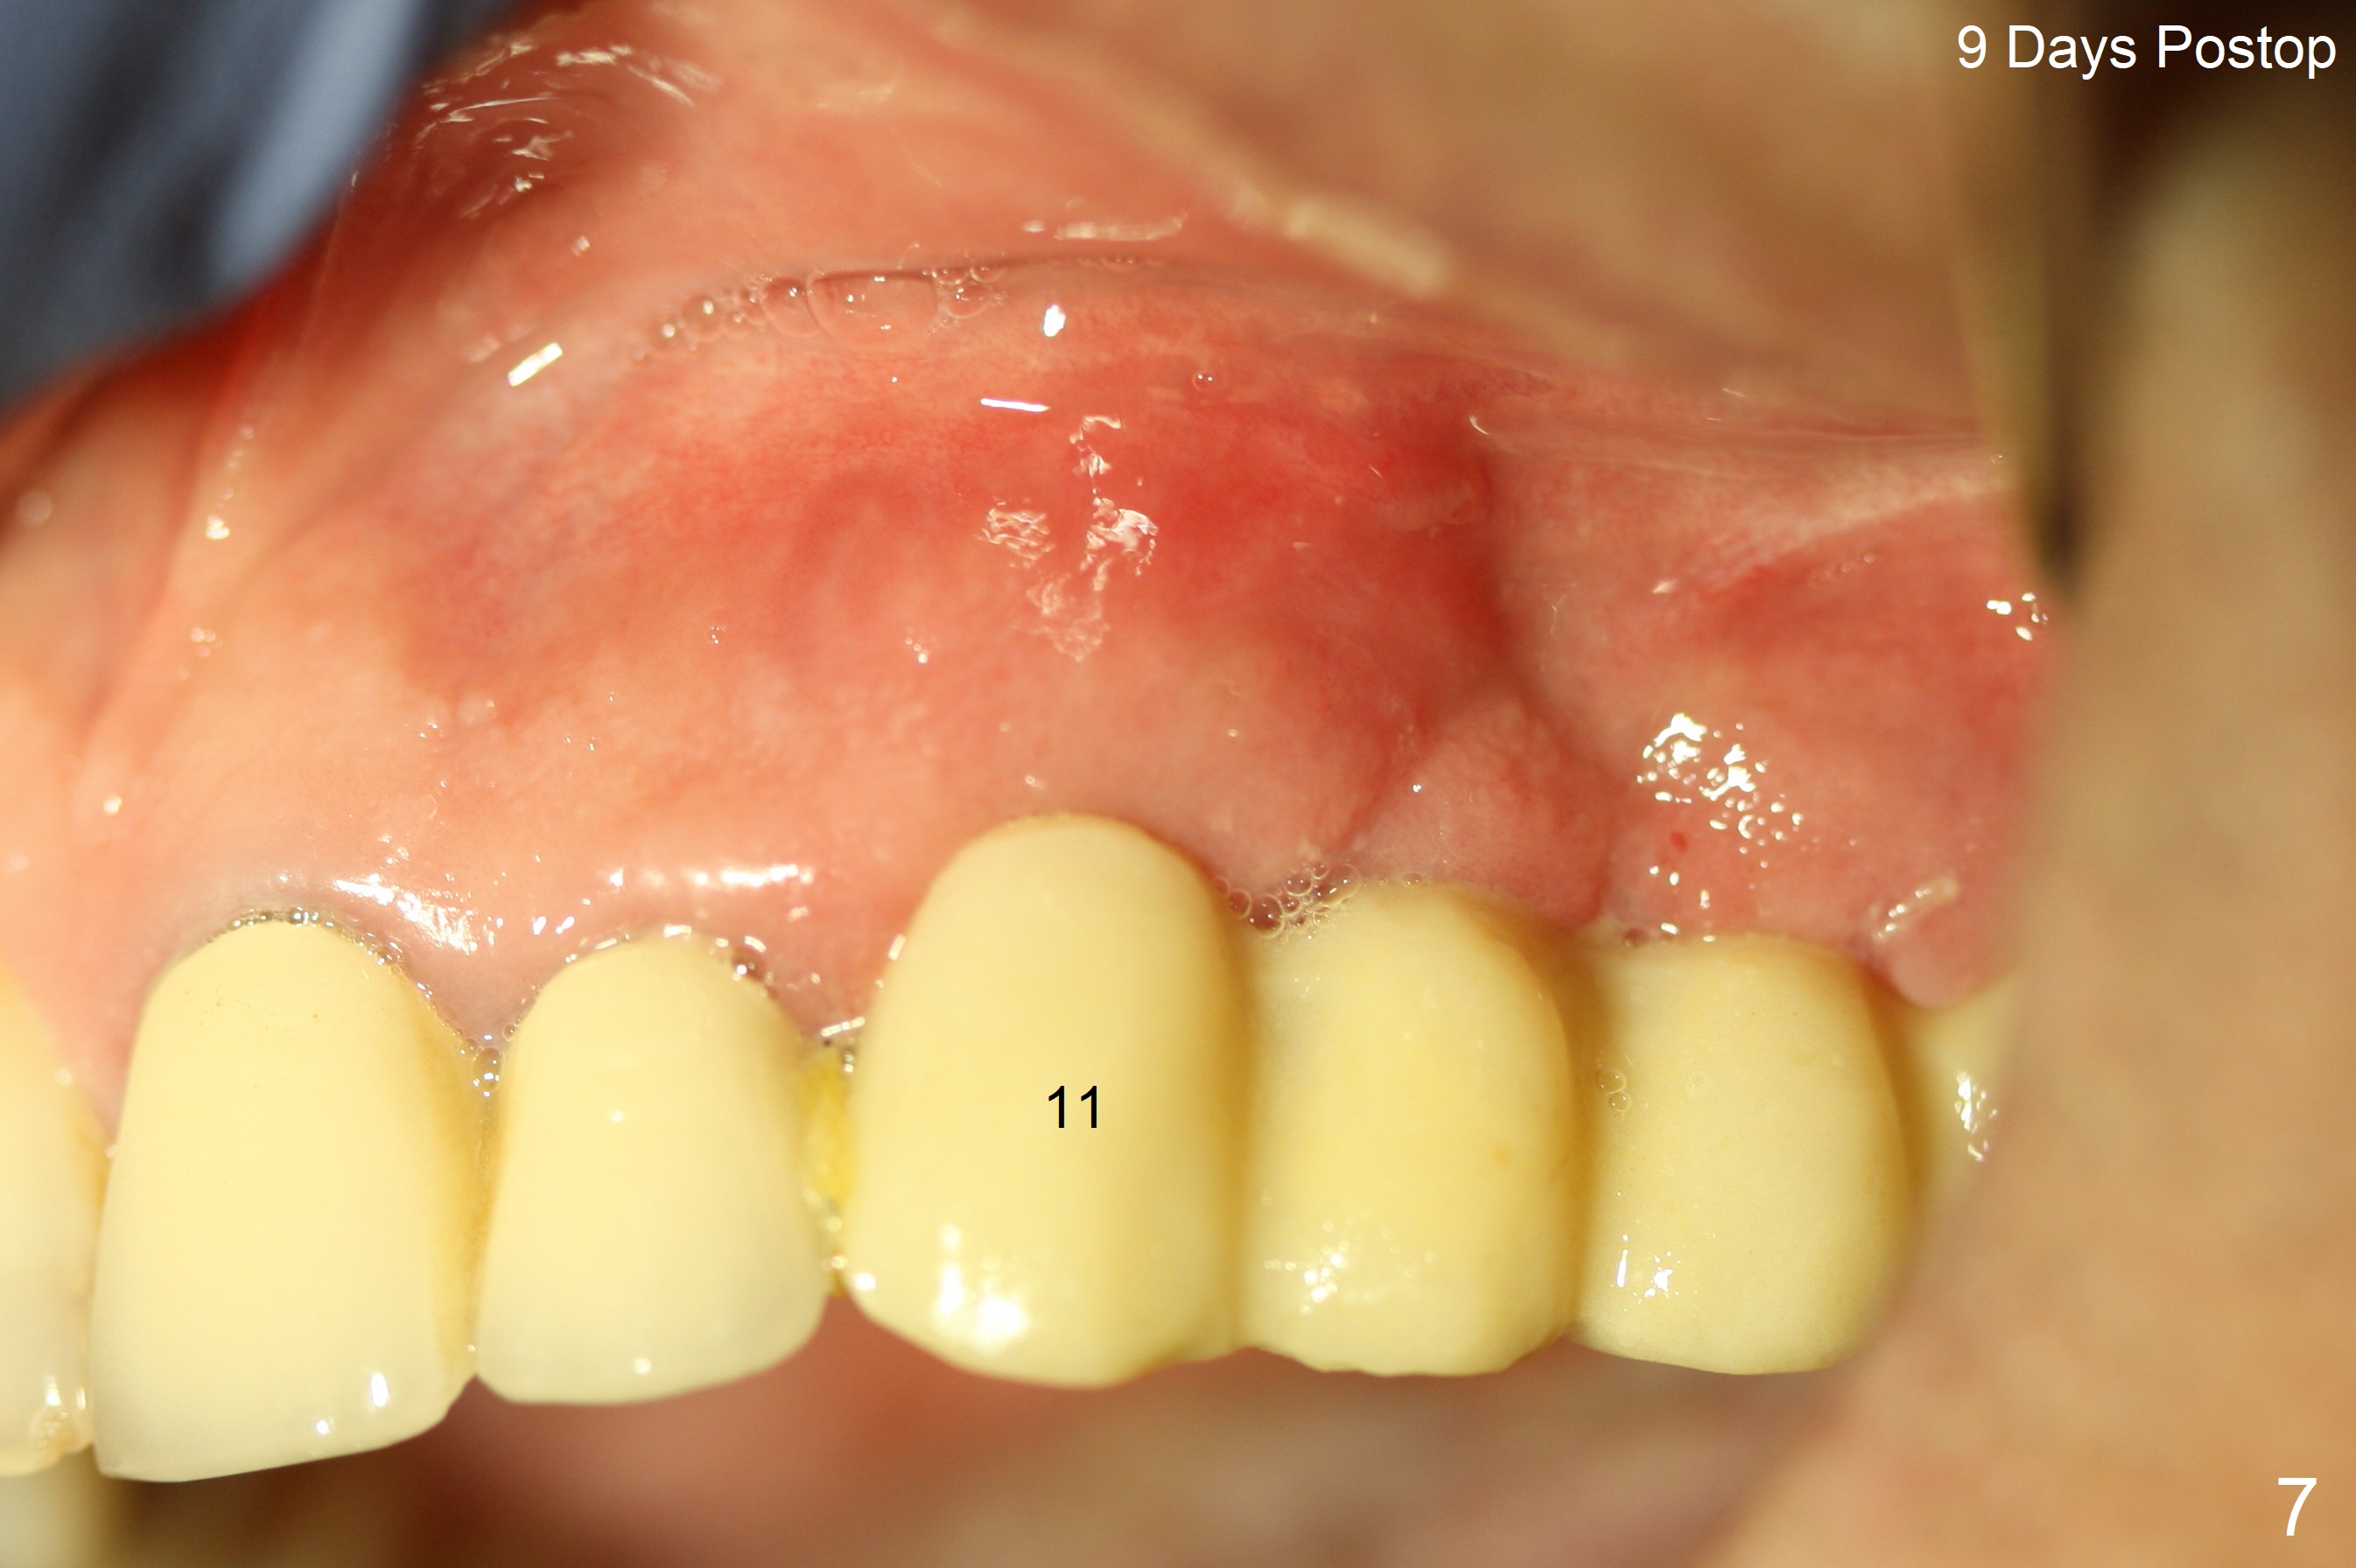

The edentulous ridge is narrow between the residual roots of #11 and 14 (Fig.1). Since the bone density is low in the edentulous area, DIO bone expanders are used (e.g., #1 (1/1.6 mm) Fig.2) after 1.2 mm initial drill. A 2x14(2) mm 1-piece implant is placed at #12 with 4 mm ridge width, while a 3x10 (2) mm dummy implant is partially placed after use of Bone Expander #2 (1.3/2.3 mm). The latter is replaced by a definitive one (3x12(2) mm), while the one at #12 is placed deeper (Fig.4). After extraction and placement of PRF and Vanilla Graft for sinus lift (Fig.4 black *), a 5x10 mm 2-piece implant is placed at #14, while a dummy implant is placed at #11 (Fig.4,5). As the osteotomy at #11 is 4.9 mm longer than the dummy (Fig.5), a definitive one is 3 mm longer (Fig.6). Osteogen plug is placed in the apical portion of each socket at #11 and 14, while Vanilla and Osteogen are packed in the coronal portion of the socket (Fig.4,6 *). Although primary stability of each implant is not high (30/40 Ncm), splinted provisional with occlusal clearance seems to be sufficient for implant osteointegration. There is no discomfort 9 days postop (Fig.7). Impression is taken 3 months postop, since he plans to return to home country for business (Fig.8). Single unit crowns are cemented 4 months postop (Fig.9,10). The abutment screw at #14 needs retightening 6 months post cementation. The access hole slightly buccal. Chewing pain at #12 is reduced after occlusal adjustment 6.5 months post cementation (Fig.11).